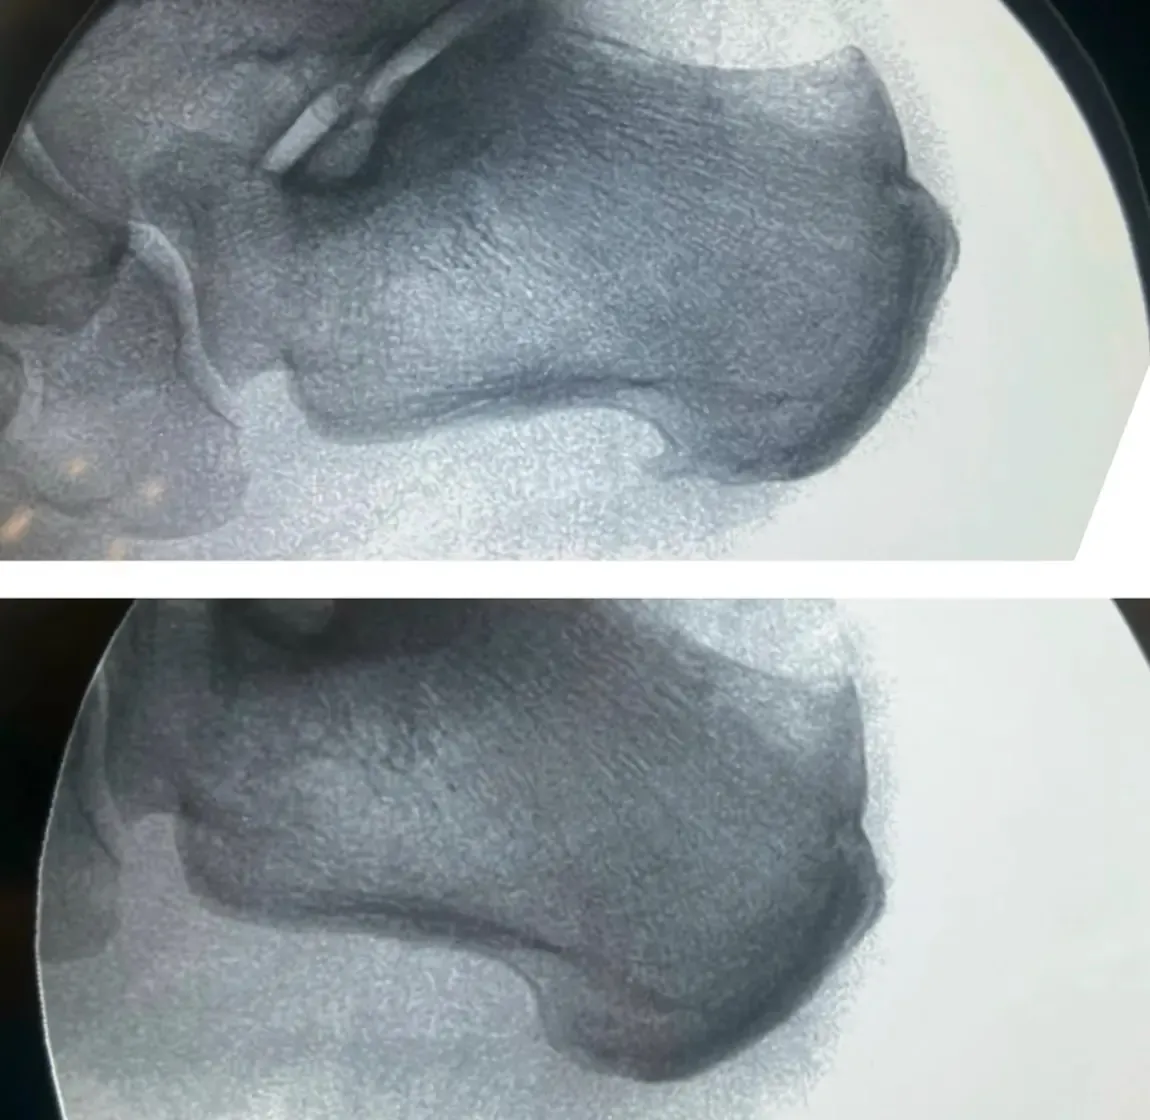

¿Es lo mismo tener fascitis plantar que un espolón calcáneo?

A menudo se asocia la fascitis plantar con la presencia de un espolón calcáneo. Sin embargo, estudios recientes han demostrado que la presencia de un espolón en las radiografías no tiene importancia clínica, ya que muchos pacientes con espolón calcáneo no presentan dolor.